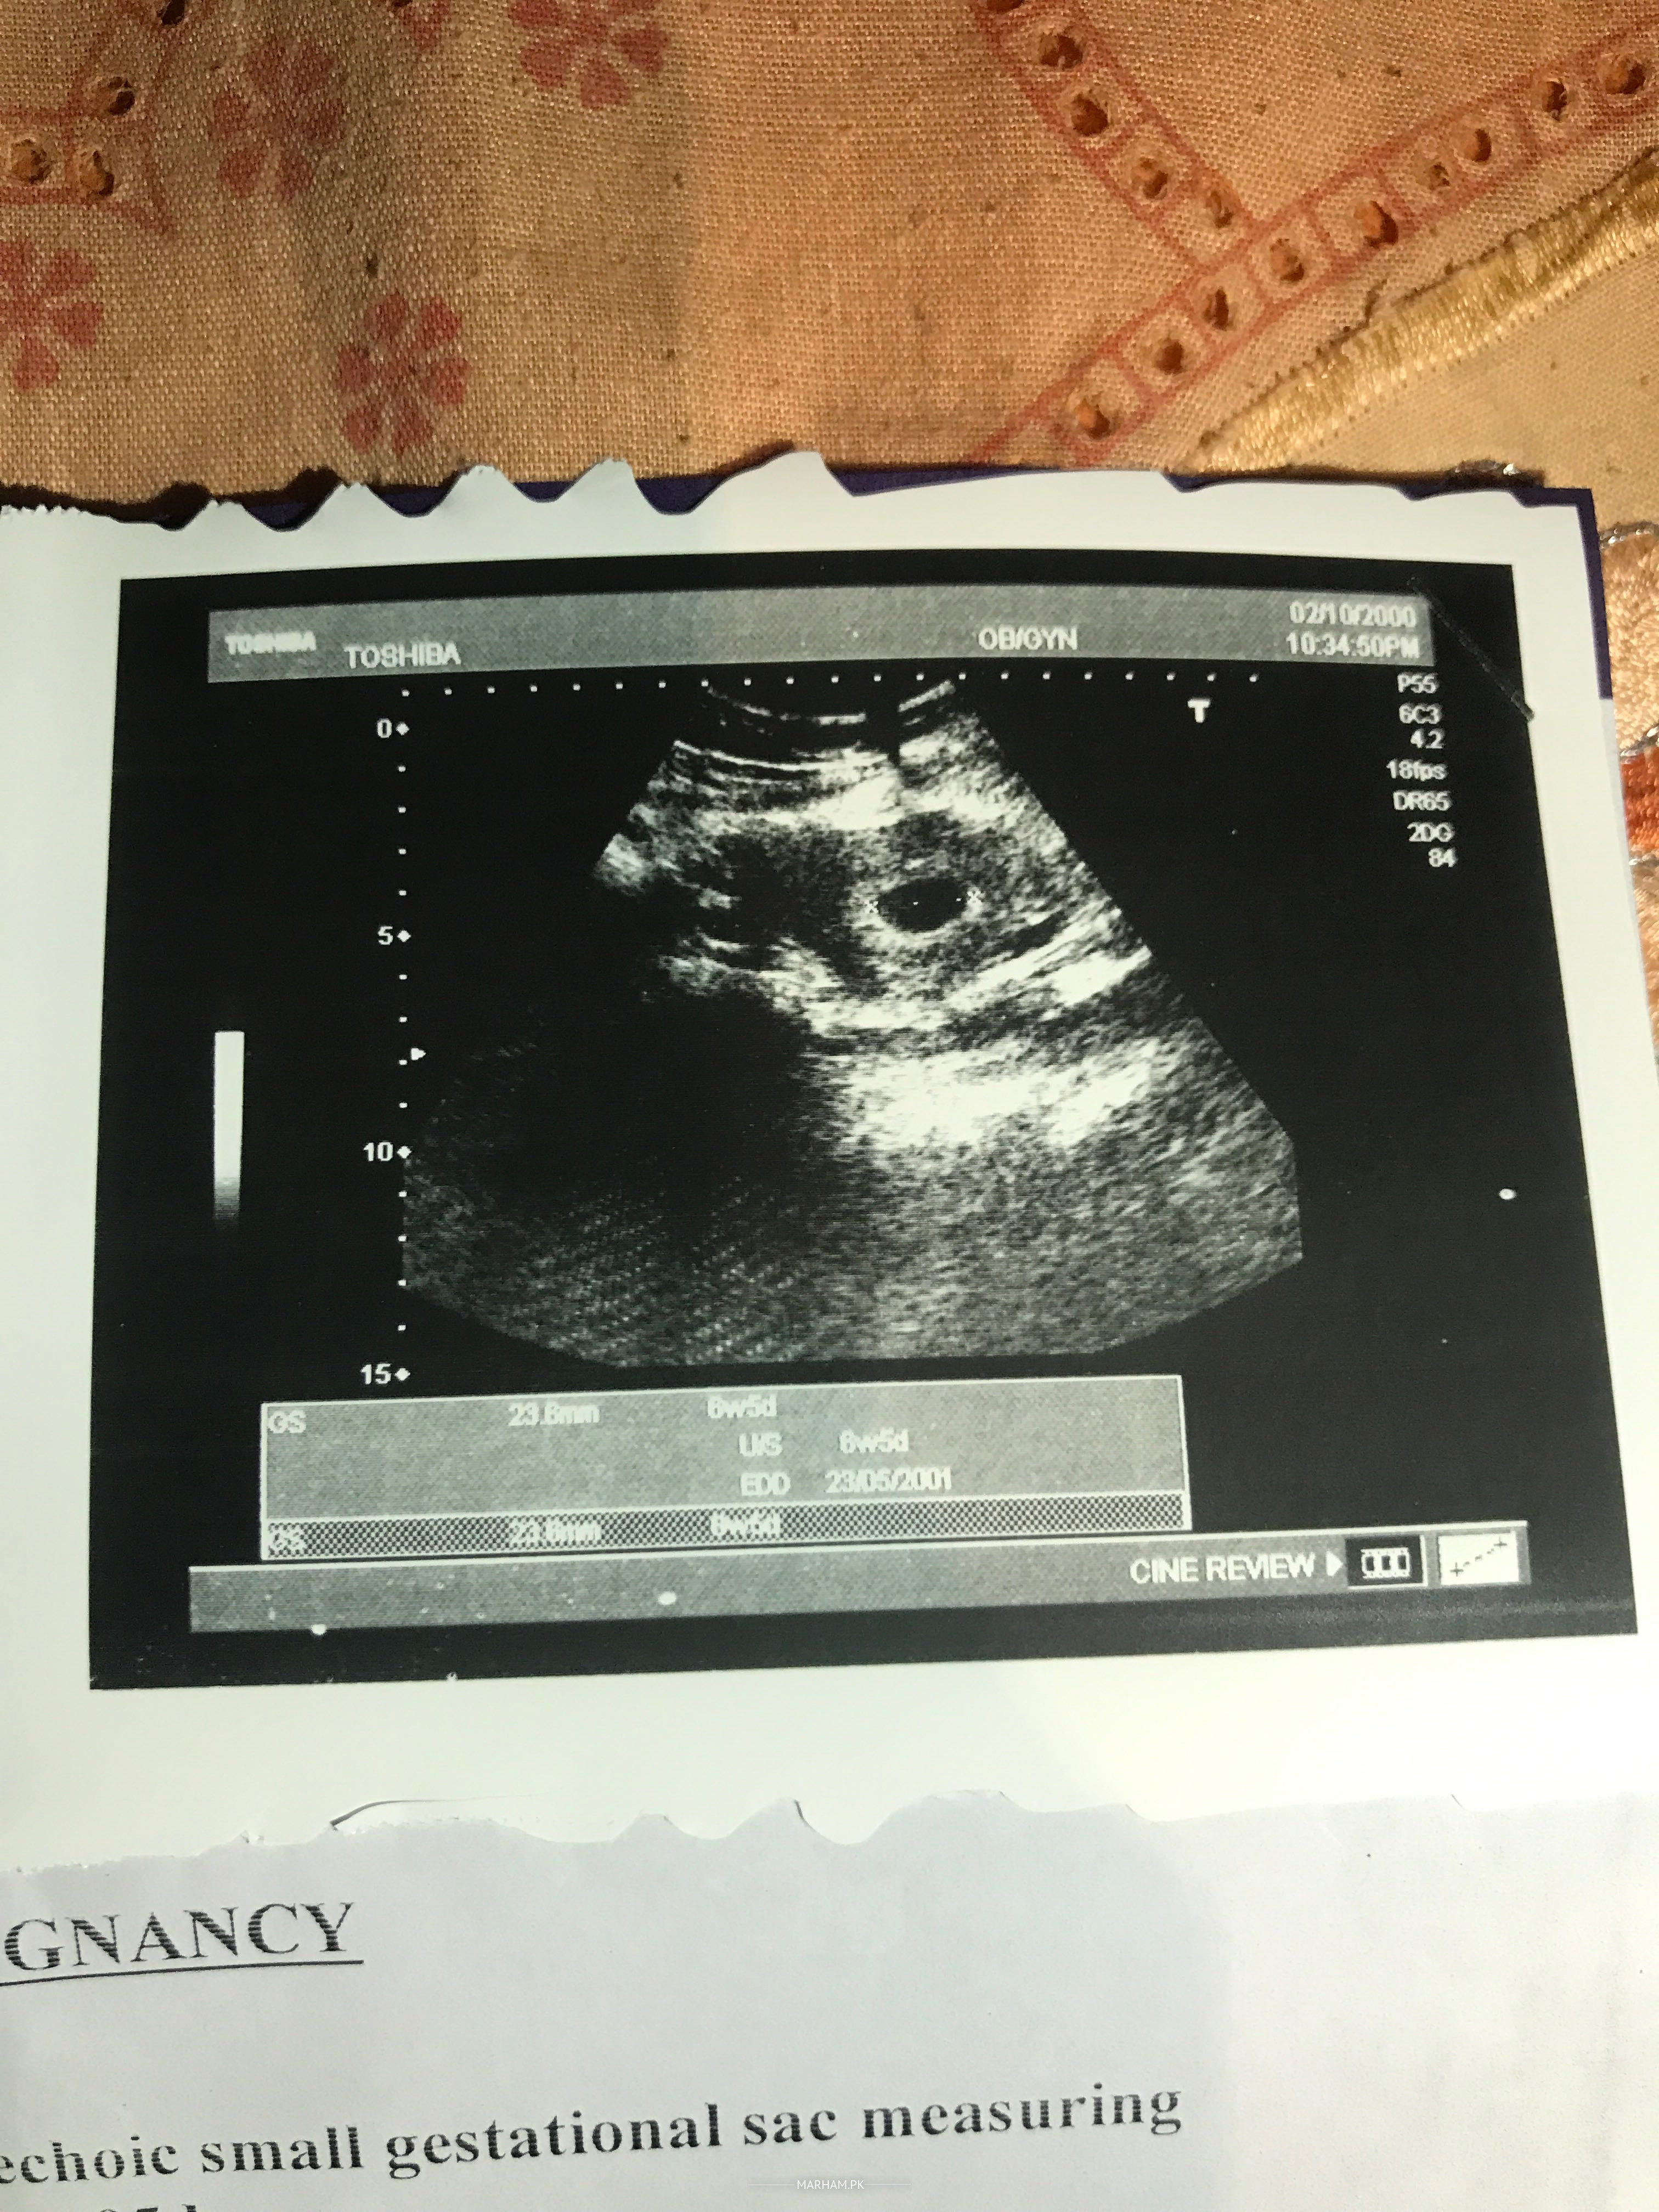

I’m 9 weeks 4 days pregnant according to my LMP which is 21st May but current ultrasound shows 6 weeks. Gestational sac is present but baby didn’t grow no embryo present inside the sac it seems empty. Doc. told me the possibilities of blighted ovum and told me about DnC. I don’t know what to do next? Should i continue the pregnancy? Or consult for the DnC?

Sac size is smaller to go for termination. Do scan in two weeks and see.